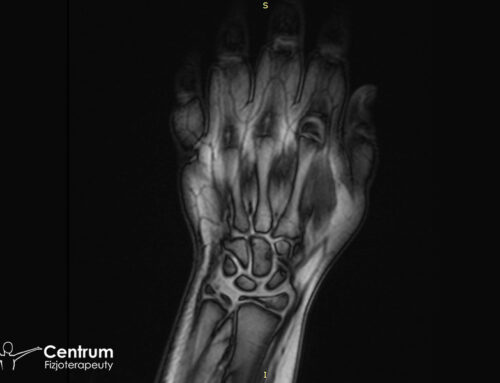

Wymienione wyżej objawy złamania rzepki mogą pojawiać się także przy wielu innych kontuzjach stawowych kolana. Uznaje się, że staw kolanowy należy do najtrudniejszych struktur diagnostycznych w ciele człowieka, dlatego przy powyższym obrazie klinicznym należy wykonać dodatkowe badania. Podstawą jest RTG, choć warto wzbogacić je w USG stawu kolanowego, które może nie tylko potwierdzić złamanie, ale i uwidocznić odłamane fragmenty rzepki czy uszkodzone struktury więzadłowe. Jeszcze dokładniejszy obraz sytuacji uzyskamy decydując się na tomografię komputerową.